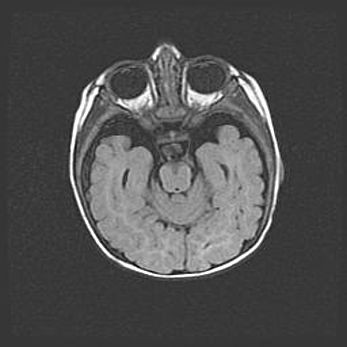

Наружная гидроцефалия с возможной атрофией височных областей.

Возраст: 28 дней

Вес: 3670 г

Пол: мужской

Окружность головы: 38 см

Срок гестации: 40 недель

Гидроцефалия головного мозга у новорожденных – это заболевание, которое характеризуется скоплением избыточного количества спинномозговой жидкости в желудочковой системе головного мозга в результате затруднения её перемещения от места выработки к месту поглощения в кровеносную систему или вследствие нарушения абсорбции. При открытой наружной форме гидроцефалии у новорожденных расширяются и переполняются субарахноидные пространства.

При нормотензивных  формах,  которые,  как  правило,  являются  следствием  перенесенных ишемических  повреждений  паренхимы  мозга,  возможно  сочетание микроцефалии  с нормотензивной гидроцефалией. В основе данных изменений лежит атрофия больших полушарий с преимущественной  локализацией  в  лобно-височных  областях.